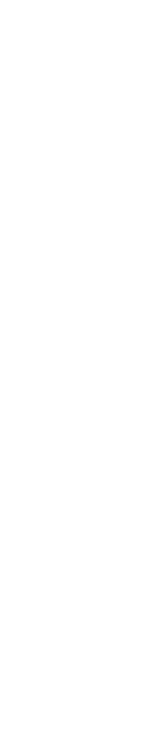

Pour effectuer une autopsie à des fins de diagnostic :

- Sélectionnz quelques porcs ayant de la fièvre (supérieure ou égale à 39,7) et les abattre. Les porcs marqués pendant la visite pourraient être des candidats.

- Les porcs trouvés morts ne sont pas aussi utiles. Ils sont souvent en mauvaise état et souffrent de maladies chroniques.

- Il faut une surface solide qui peut être nettoyée, un couteau à désosser bien aiguisé (pas une lame de scalpel), des gants et, si vous prélevez des échantillons, des sacs, de l'alcool et un briquet.

- L'ordre et l'hygiène sont essentiels :

- Ouvrez d'abord le thorax pour vous assurer que les poumons ne sont pas contaminés.

- puis le cerveau

- et ensuite l'intestin, dans cet ordre.

Si vous examinez d'abord l'intestin, vous retrouverez ce qu'il contient dans le reste des tissus (figure 2).

Figure 2 : Pour éviter toute contamination croisée lors du prélèvement d'échantillons de cerveau, suivez un ordre strict pendant l'autopsie et utilisez un couteau robuste stérilisé à la flamme (et refroidi) pour ouvrir le crâne et des pinces/ciseaux stérilisés à la flamme et refroidis pour retirer le cerveau.

Collecte des échantillons : Chaque échantillon doit être placé dans un sac séparé pour éviter toute contamination croisée. La collecte doit être effectuée avec soin et il faut utiliser de l'alcool et un briquet pour flamber les instruments.